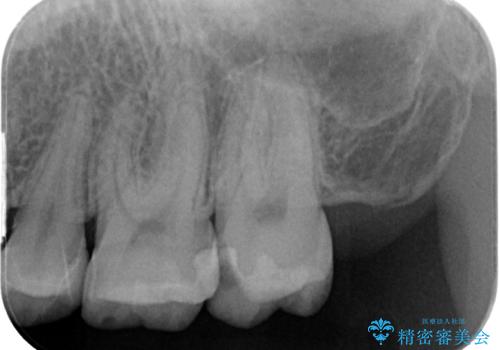

- プラスチックの詰め物が取れたとのことで来院された患者様です。神経の状態を検査し、正常な状態を確認してから残っている自分の歯の量を考慮しセラミックインレーにて修復しました。

拡大鏡視野下でコンポジットレジン、虫歯の除去を行い、セラミックインレーに適した形に整えました。